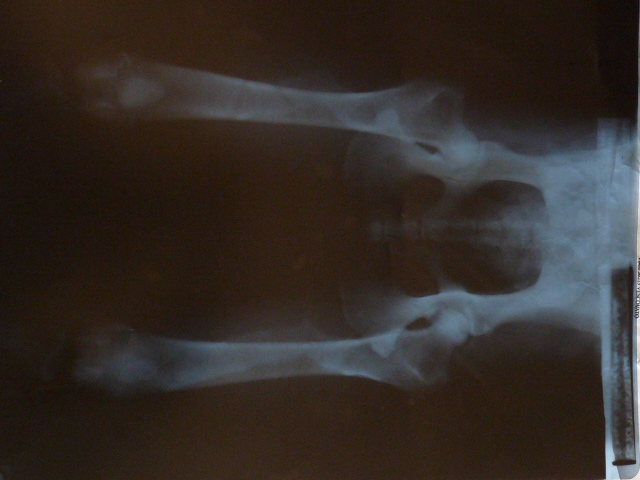

Tares